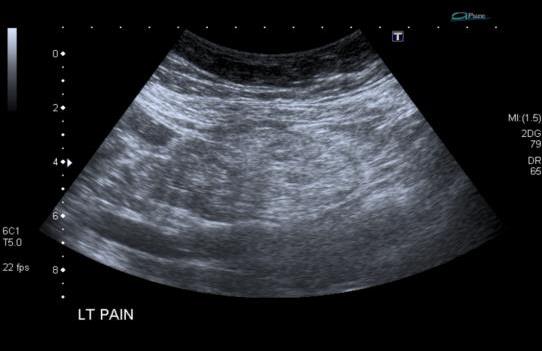

Representative sonographic images of the abdominal scan are shown below:

![]() |

Figure 2. Longitudinal image of the left kidney |